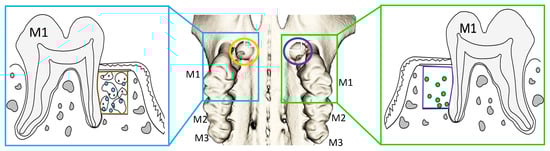

3.2. Radiological and Structural Observations